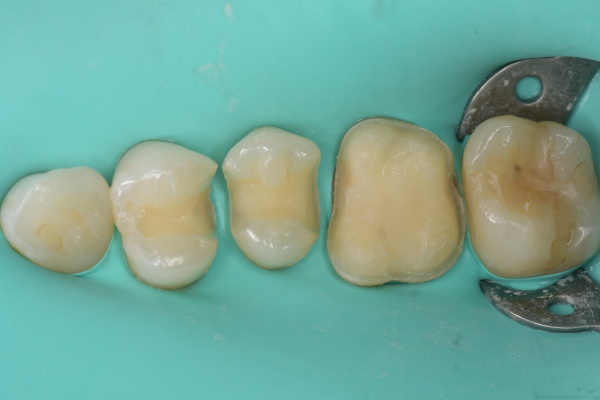

セラミック治療の治療例です。虫歯になった歯を、見た目もきれいに治したいとのご希望で来院されました。当院にて、3本同時にセラミックによる修復を実施しました。染め出しにより取り残しや汚れを確認し、プラークなどを除去したうえでセラミックを装着しています。オキシガードは、過酸化物と還元剤による化学重合反応により、歯科接着用レジンセメント表面の未重合層を硬化させる材料です。さらに、未重合層を空気から遮断することで確実な硬化を促します。接着効率をあげるためにラバーダムを使用し治療を行っております。

術前から術後までの治療の流れ

虫歯処置後